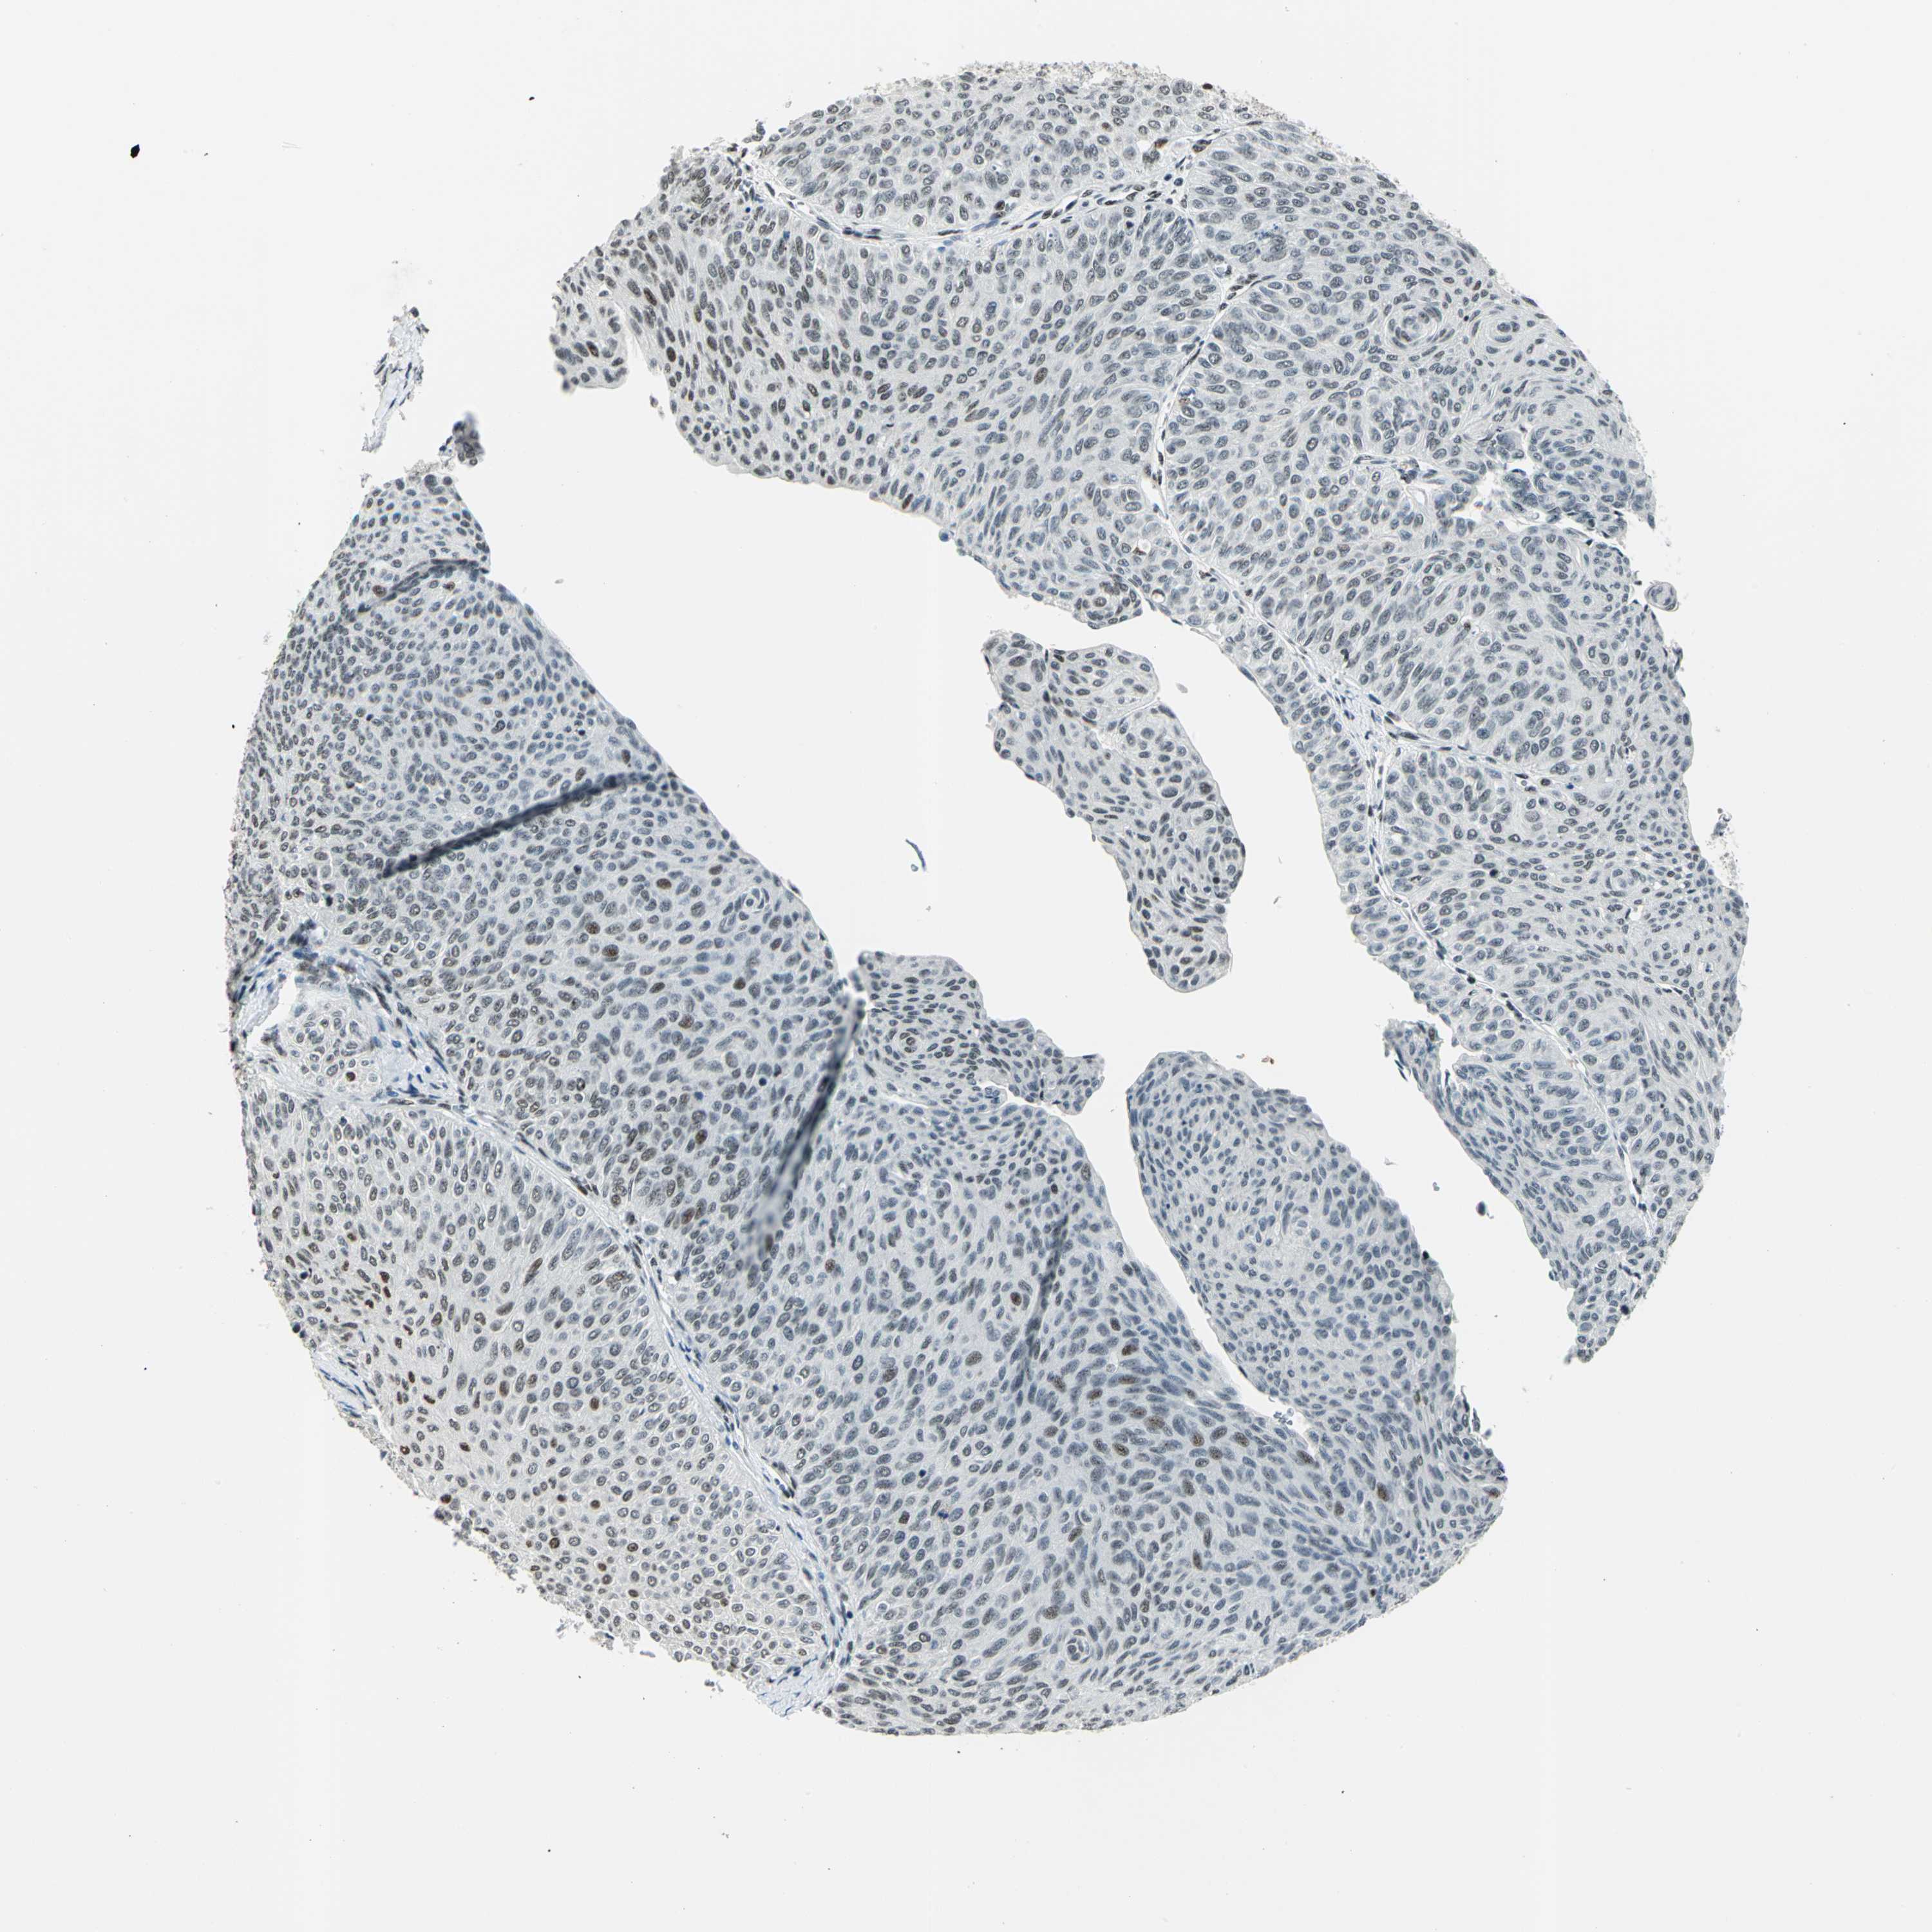

UROTHELIAL CANCER - Protein expressioni

A mouse-over function shows sample information and annotation data. Click on an image to view it in a full screen mode. Samples can be filtered based on level of antibody staining by selecting one or several of the following categories: high, medium, low and not detected. The assay and annotation is described here.

Antibody stainingi

Antibody staining in the annotated cell types in the current human tissue is reported as not detected, low, medium, or high, based on conventional immunohistochemistry profiling in selected tissues. This score is based on the combination of the staining intensity and fraction of stained cells.

Each image is clickable and will lead to virtual microscopy that enables deeper exploration of all samples and also displays staining intensity scores, fraction scores and subcellular localization as well as patient and tissue information for each sample.

Antibody HPA006104

Staining

High

Medium

Low

Not detected

Intensity

Strong

Moderate

Weak

Negative

Quantity

>75%

75%-25%

<25%

None

Location

Nuclear

Cytoplasmic/membranous

Cytoplasmic/membranous,nuclear

Urothelial carcinoma, Low grade

Urothelial carcinoma, High grade